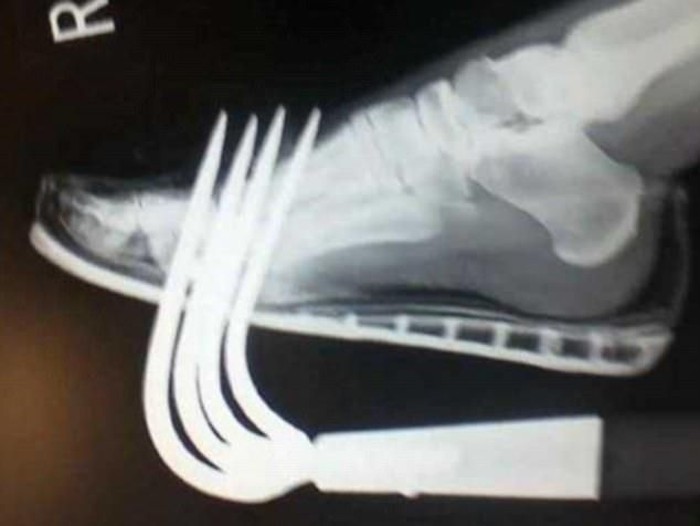

Menurut sang pengunggah meski foto rontgen tersebut terlihat menyeramkan namun aslinya kaki pasien tidak mengalami kerusakan berat. "Garpu itu entah bagaimana sama sekali tidak mengenai tulang yang ada," ujarnya.

"Ini adalah contoh utama mengapa Anda tidak boleh membiarkan alat berkebun bergeletakan di mana saja. Selalu taruh alat di tempat yang mudah dilihat... Pakai sepatu yang kuat saat berkebun, jangan sendal saja seperti yang pasien ini lakukan," kata Joe seperti dikutip dari Daily Mail, Rabu (13/12/2017).

Lebih jauh Joe mengatakan bagi orang-orang yang mengalami hal serupa agar jangan panik dan berusaha mencabut apapun yang tertancap ke dalam tubuh sendiri. Hal ini untuk mencegah terjadinya pendarahan lebih parah.

"Selama benda itu masih di dalam tubuh, dia akan menahan pendarahan dengan menyumbat pembuluh darah dan arteri yang tertembus. Kalau dicabut, maka Anda menghilangkan apa yang bisa menahan pendarahan," kata Joe.

Beri tekanan pada luka di tempat masuk atau keluarnya alat dalam tubuh sambil menunggu bantuan medis. Hal yang harus dikhawatirkan adalah terjadinya infeksi tetanus oleh bakteri yang biasanya ada di tanah.